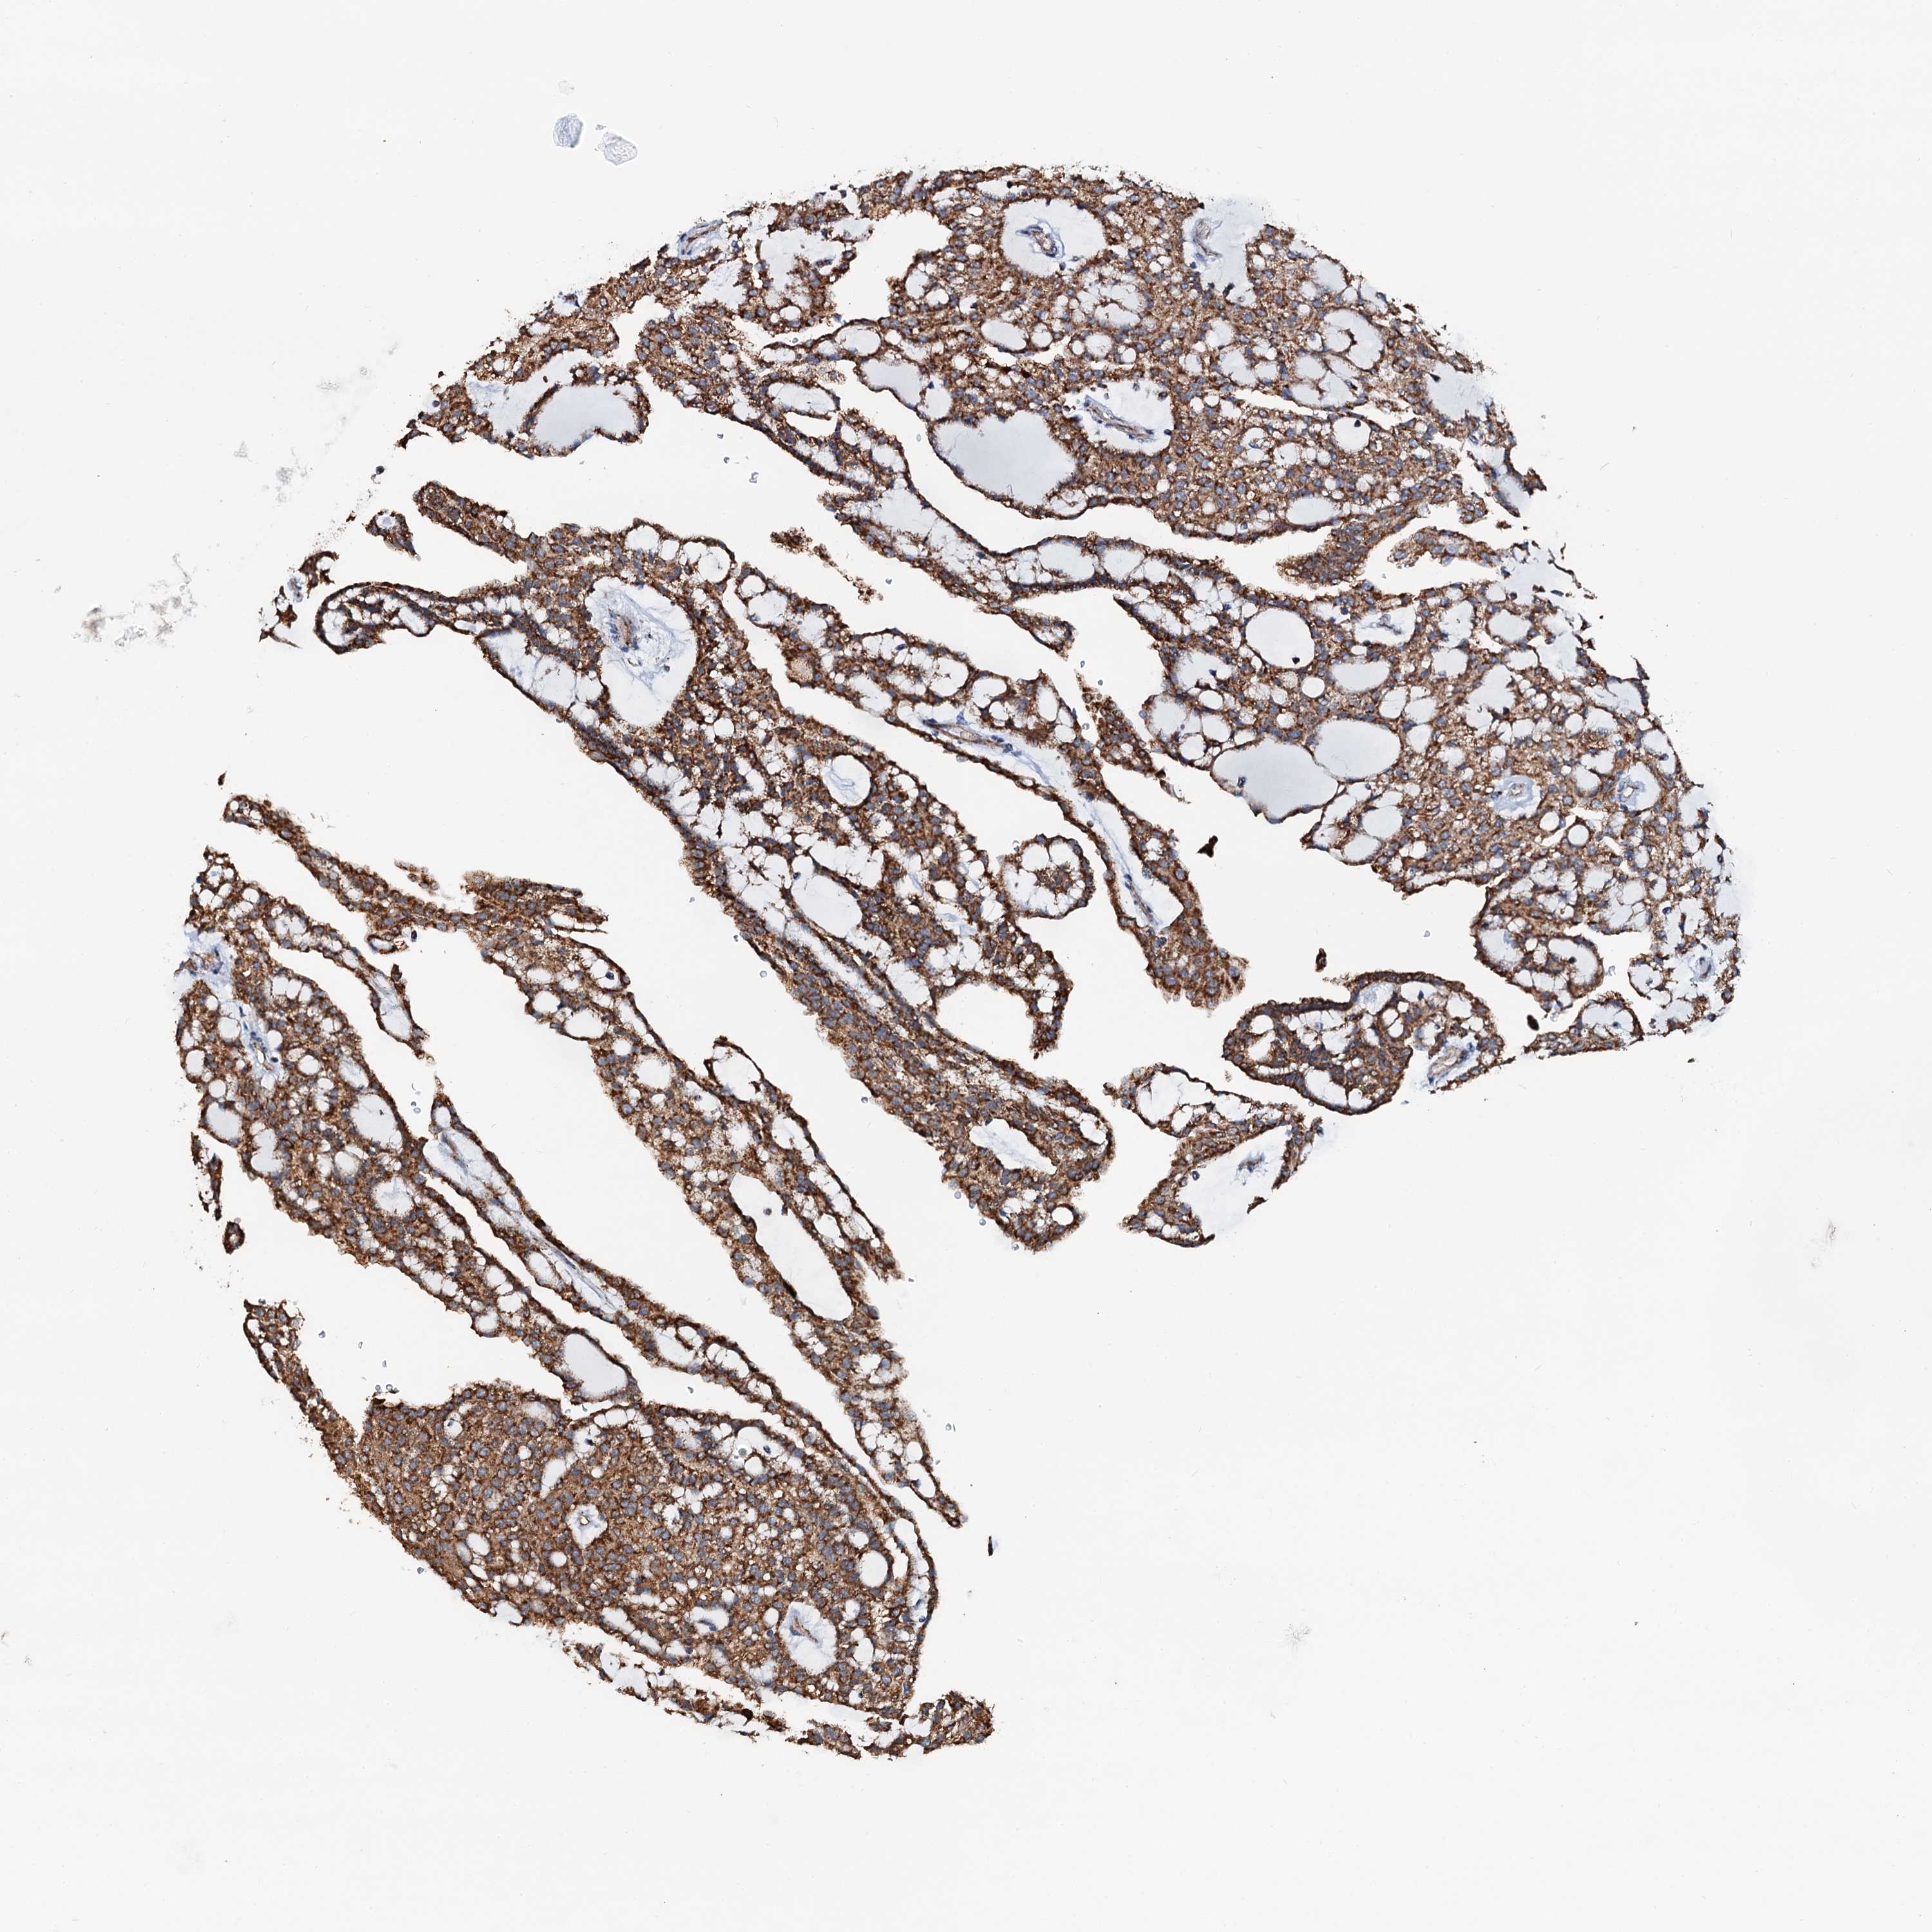

KIDNEY CHROMOPHOBE (TCGA) - Interactive survival scatter ploti

The Survival Scatter plot shows the clinical status (i.e. dead or alive) for all individuals in the patient cohort, based on the same data that underlies the corresponding Kaplan-Meier plots. Patients that are alive at last time for follow-up are shown in blue and patients who have died during the study are shown in red.

The x-axis shows the expression levels (FPKM) of the investigated gene in the tumor tissue at the time of diagnosis. The y-axis shows the follow-up time after diagnosis (years). Both axes are complimented with kernel density curves demonstrating the data density over the axes. The top density plot shows the expression levels (FPKM) distribution among dead (red) and alive patients (blue). The right density plot shows the data density of the survived years of dead patients with high and low expression levels respectively, stratified using the cutoff indicated by the vertical dashed line through the Survival Scatter plot. This cutoff is automatically defined based on the FPKM cutoff that minimizes the p-score. The cutoff can be changed by dragging the vertical line or by entering a cutoff value in the square labeled "Current cut-off".

Under the Survival Scatter plot the p-score landscape (black curve; left axis) is shown together with dead median separation (red curve; right axis). Dead median separation is the difference in median mRNA expression between patients who have died with high and low expression, respectively. It is calculated as follows: median FPKM expression of dead patients with high expression - median FPKM expression of dead patients with low expression. This is intended to aid the user in visually exploring custom cutoffs and the associated p-scores and dead median separation.

Individual patient data is displayed and can be filtered by clicking on one or more of the category buttons on the top of the page. Categories describing expression level and patient information include: high, low, alive, dead, female, male and tumor stages. The scale of the x-axis can be toggled between linear and log-scale by clicking on the "x log" button. Mouse-over function shows TCGA ID, patient information and mRNA expression (FPKM) for each patient.

& Survival analysisi

Kaplan-Meier plots summarize results from analysis of correlation between mRNA expression level and patient survival. Patients were divided based on level of expression into one of the two groups "low" (under cut off) or "high" (over cut off). X-axis shows time for survival (years) and y-axis shows the probability of survival, where 1.0 corresponds to 100 percent.

AAGAB is not prognostic in Kidney Chromophobe (TCGA)

Best expression cut offi

: 41.27

P scorei

N/A

TCGA RNA samplesi

RNA-seq data is reported as average FPKM (number Fragments Per Kilobase of exon per Million reads), generated by the The Cancer Genome Atlas (TCGA) .

Normal distribution across the dataset is visualized with box plots, shown as median and 25th and 75th percentiles. Points are displayed as outliers if they are above or below 1.5 times the interquartile range. FPKM values of the individual samples are presented next to the box plot.

Average pTPM 32.0

Number of samples 64